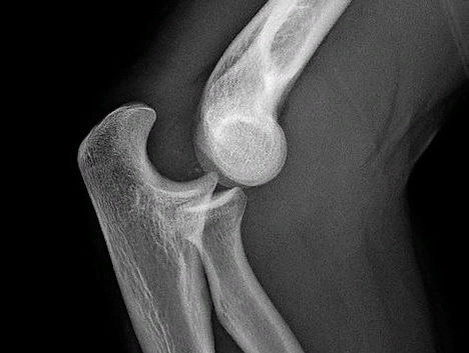

Вывих - смещение суставных концов костей, при котором утрачивается их правильное соприкосновение. Вывихи обуславливаются чрезмерным движением в суставе (при сильном ударе в область сустава, падении). Как правило, вывихи сопровождаются разрывом суставной сумки и разъединением сочленяющихся суставных поверхностей. Попытки сопоставить части безуспешны и сопровождаются сильнейшей болью и пружинящим сопротивлением. Вправление травматического вывиха должно быть как можно более ранним. Чаще всего вывихи бывают плечевого и локтевого суставов, большого пальца и тазобедренного сустава. ПРИЗНАКИ: ★ Изменение формы сустава

Вывихи обуславливаются чрезмерным движением в суставе (при сильном ударе в область сустава, падении). Как правило, вывихи сопровождаются разрывом суставной сумки и разъединением сочленяющихся суставных поверхностей.

Чаще всего вывихи бывают плечевого и локтевого суставов, большого пальца и тазобедренного сустава.